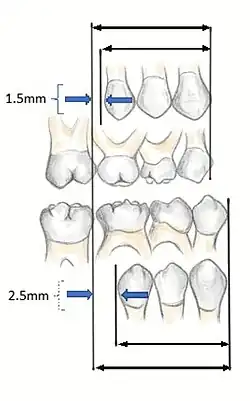

In order to fully understand the development of occlusion and malocclusion, it is important to understand the premolar dynamics in the mixed dentition stage. The mixed dentition stage is when both primary and permanent teeth are present. The permanent premolars erupt ~9–12 years of age, replacing the primary molars. The erupting premolars are smaller than the teeth they are replacing and this difference in space between the primary molars and their successors (1.5mm for maxillary, 2.5mm for mandibular[7]), termed Leeway Space. This allows the permanent molars to drift mesially into the spaces and develop a Class I occlusion.